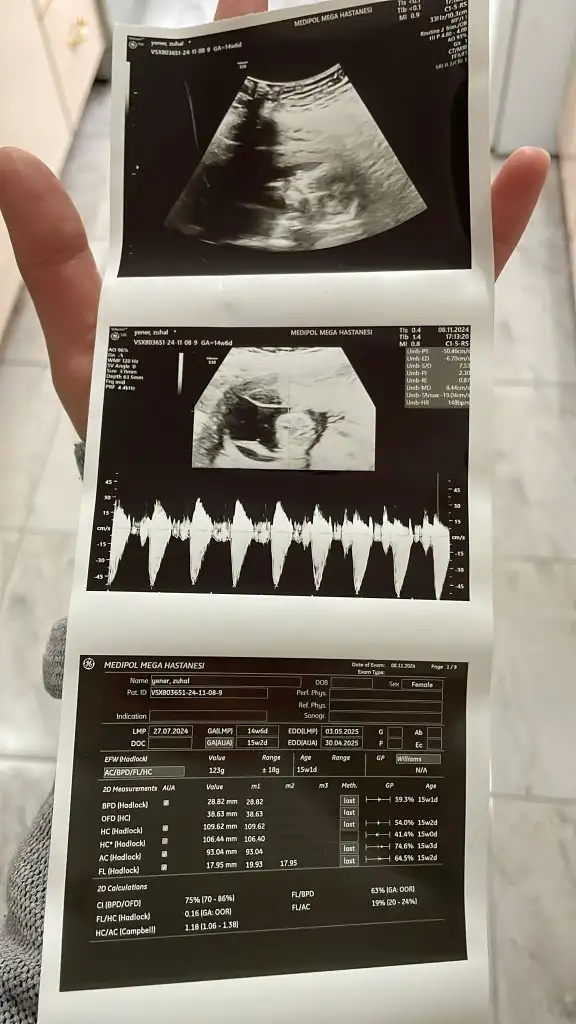

Kızlarım merhaba benim dee 13+2 cinsiyet tahmininizi alabilir miyim

Kız gibiKızlarım merhaba benim dee 13+2 cinsiyet tahmininizi alabilir miyim